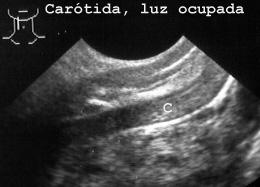

La carótida se observa siempre, esté libre (Fig 27)

27CAROTL.JPG (13492 bytes)

Fig 27

u obstruida por un tromboembolo o coagulo postmortem (Fig 28).

28CAROTI.JPG (18678 bytes)

Fig 28